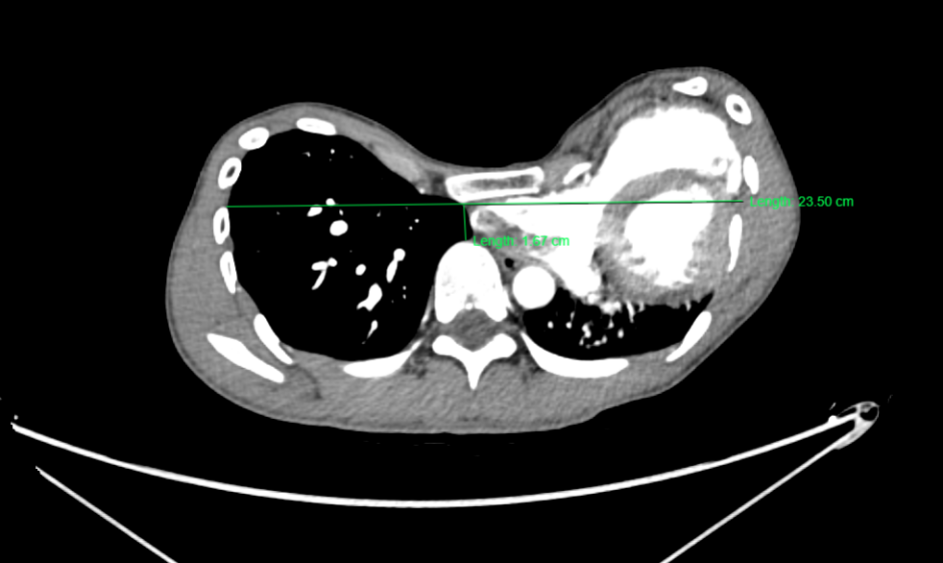

入院后检查发现小王身高190cm,体重仅65kg,胸壁呈严重凹陷畸形,胸廓凹陷最深处约6cm,胸骨下段及两侧肋骨向后极度凹陷形成漏斗状,脊柱“S”型侧弯及胸椎后凸明显,面容瘦长、四肢及手指脚趾细长、高度近视。询问家族史进一步了解到小王父母均患有严重先天性疾病。辅助检查显示,心脏超声:右心受压变形,主动脉窦部已明显增宽41mm。CT提示:漏斗胸“Haller”指数高达14.07,心肺严重受压,肺功能中度受损。结合查体、家族史及辅助检查,考虑诊断为:极重度漏斗合并马凡综合征。

CT图